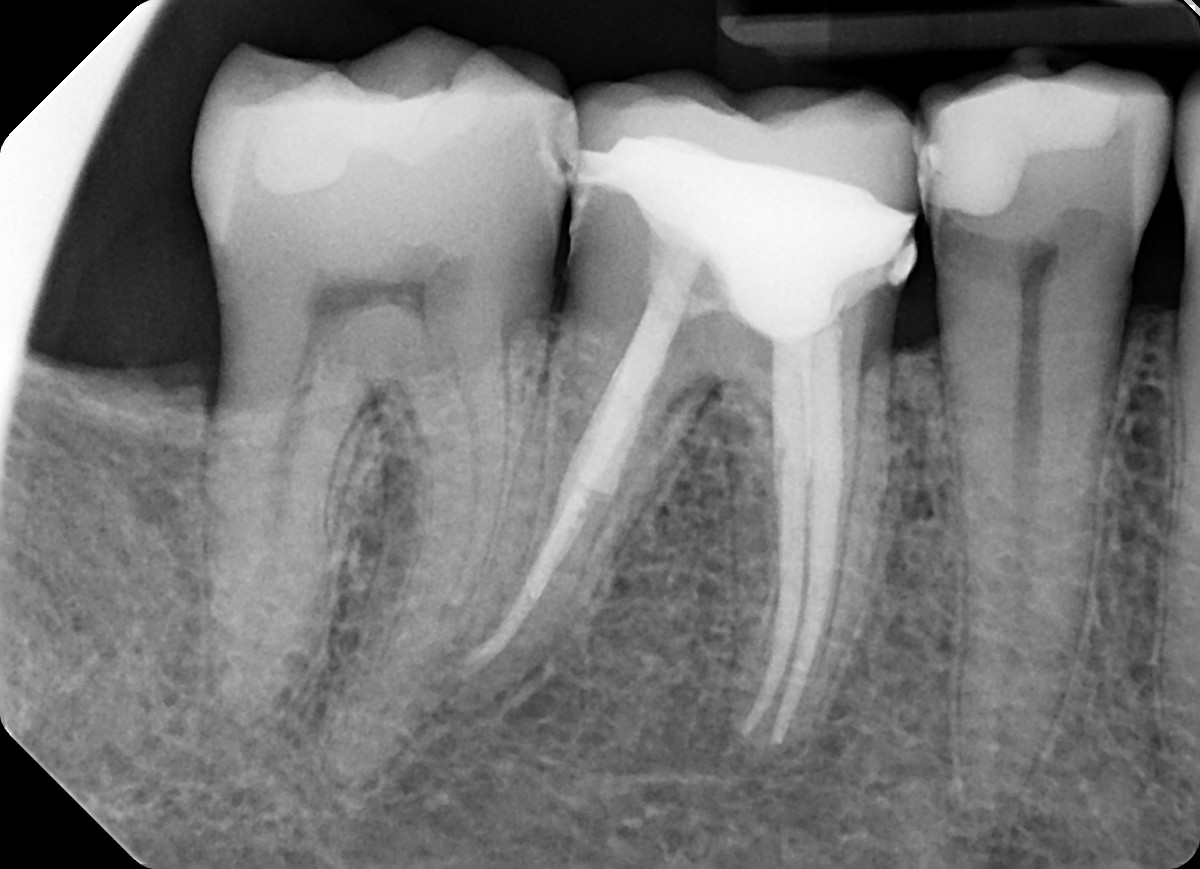

2. In the X ray bellow for which jaw periodontal bone loss is evident?